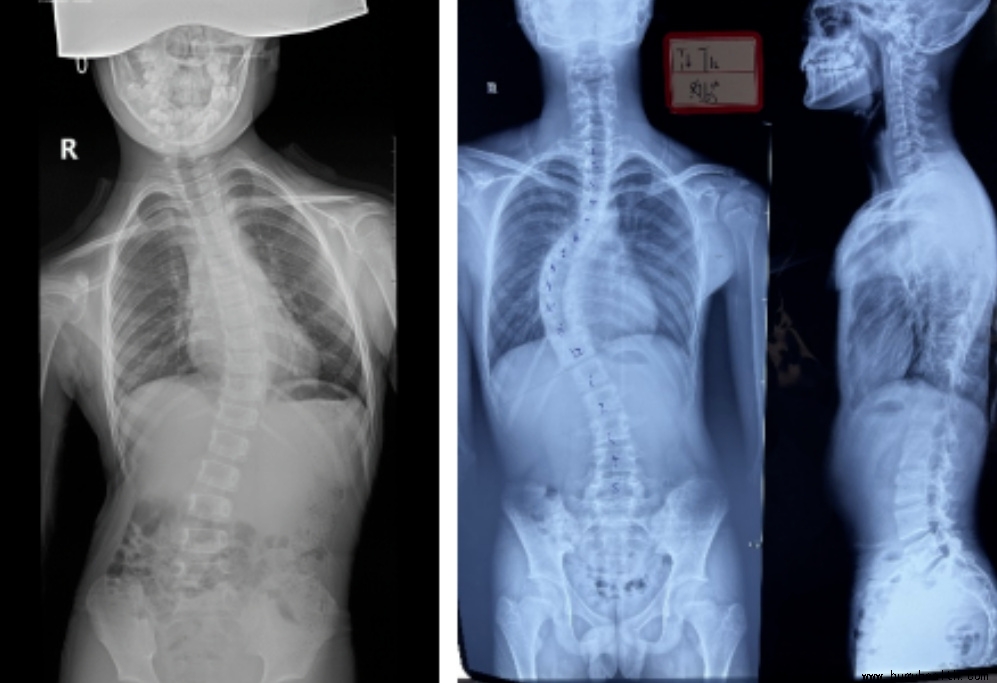

例子二:这是一个14岁的男孩,也是住校,父母常年在外务工,当父母过年回家发现孩子背部不对劲的时候,来检查侧弯已经很大很大了,孩子侧弯度数这么大也是不痒不痛,但是这个70多度的侧弯只能做手术了。

严重的畸形不仅影响孩子外观,例如高低肩、含胸驼背、剃刀背,这些都会导致自卑、抑郁、缺乏自信等心里情绪问题,还会给孩子造成心肺功能降低,例如出现呼吸困难或者呼吸急促等问题,也会出现神经压迫,当侧弯到达一定的程度时神经就会受到压迫,会出现麻木疼痛等相关神经症状,如果侧弯继续加大,在纵向力的冲击下可能会发生脊柱骨折,导致脊髓损伤可能瘫痪,甚至危及生命。

脊柱侧弯的诊断标准是cobb角大于10度,所以当家长自己在家用六部筛查法怀疑自己孩子有可能有脊柱侧弯的时候,你就应该带孩子到医院找专业的医生进行进一步确诊,当我们通过影像学确诊为脊柱侧弯的时候,我们会根据孩子的年龄、侧弯度数来建议目前孩子适合的矫正方法,目前对于脊柱侧弯的矫正大致分为三种:一是康复训练即矫形体操;二是体操加矫形支具;三是手术。